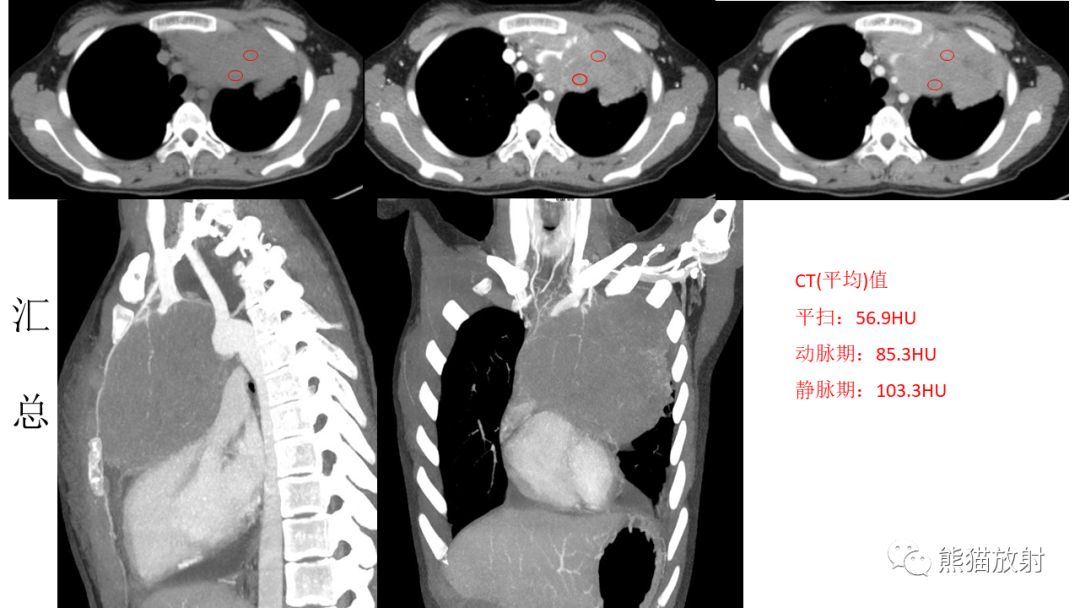

病例结果:青少年前纵隔淋巴瘤